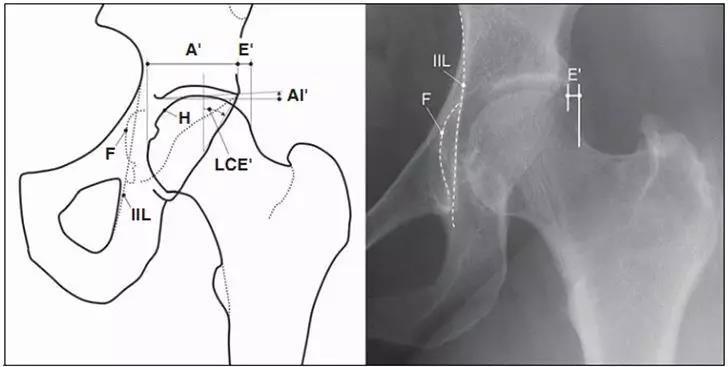

LCE角

髋关节外侧CE角(lateralcenter-edge angle,LCEA或center-edgeangle of Wiberg):根据Wiberg的描述,在骨盆前后位X线片上,C点定义为股骨头的中心,E点为髋臼最外侧处。经过C、E两点的直线与身体中线的平行线之间的夹角即为LCEA。Ogata等定义了一种新的测量方法,即取髋臼侧软骨下硬化带的外缘为E点。正常值:>25°。<20°即可诊断髋关节发育不良。但是若LCEA>45°则说明髋臼有过度覆盖的倾向。

- 中心边缘角(LCE角)正常范围为25一39;髋臼指数(AI)正常值>0;挤压指数(E/A+E)正常值<25%。

- IIL:髂坐线;AW:髋臼前壁缘;PW:髋臼后壁缘;A为股骨头被髋臼覆盖部分的宽度;E为股骨头未被髋臼覆盖部分的宽度;F为髋臼窝线。